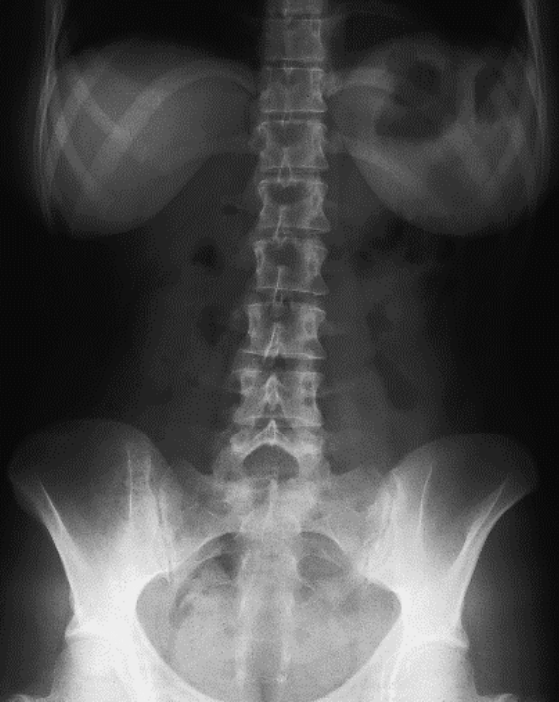

Które badanie zostało zarejestrowane na przedstawionym radiogramie?

Ilustracja do pytania 21

A. Jamy brzusznej wykonane poziomą wiązką promieniowania.

B. Płuc wykonane metodą Przybylskiego.

C. Układu moczowego z użyciem środka kontrastującego.

D. Dróg żółciowych metodą cholangiografii śródoperacyjnej.